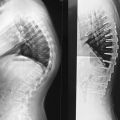

Fotos